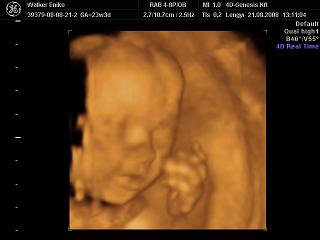

Nagyon helyesek a 4D-s fotók!!!